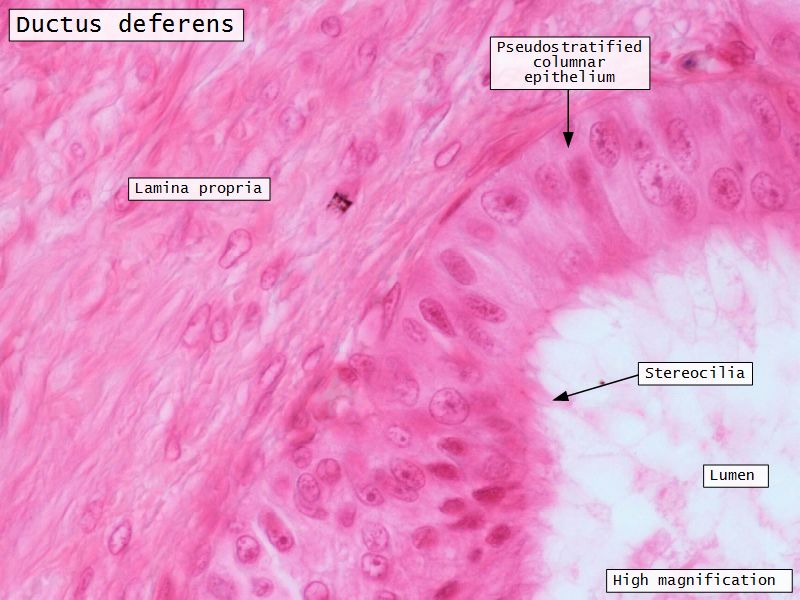

Ductus deferens

- Muscular duct with small lumen

- Lumen

- Pseudostratified columnar epithelium

- Stereocilia

- Fibroelastic lamina propria

Ductus deferens

- Longitudinal folds in

- Epithelium

- Lamina propria